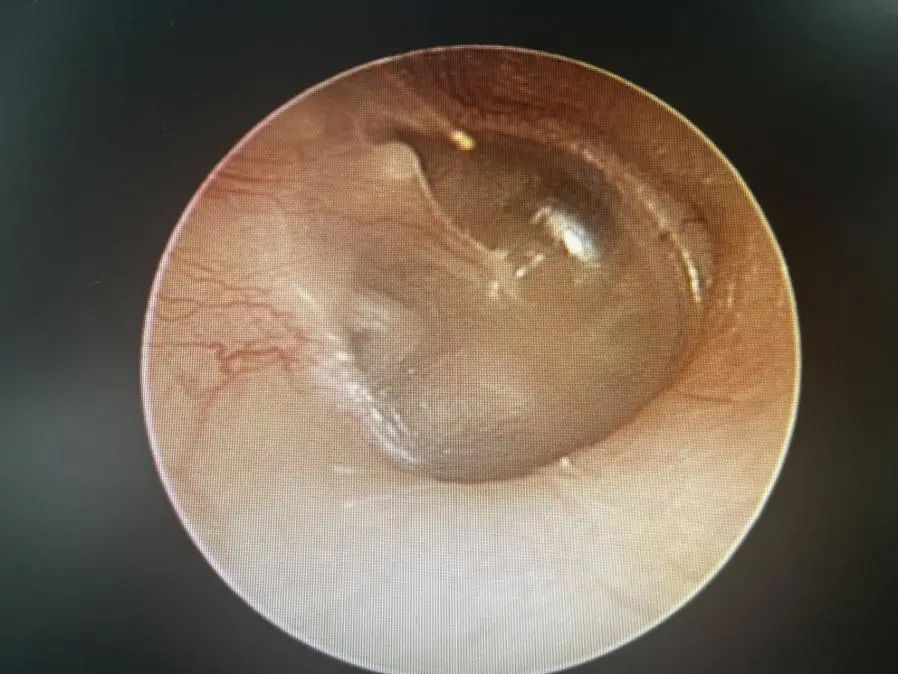

正常鼓膜